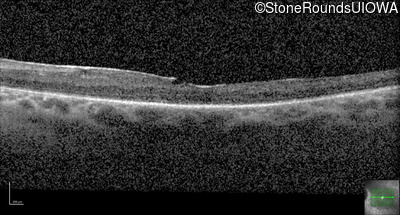

Optical Coherence Tomography - Right - 20/80 +1

Exemplar / OCT Stack

OCT Stack